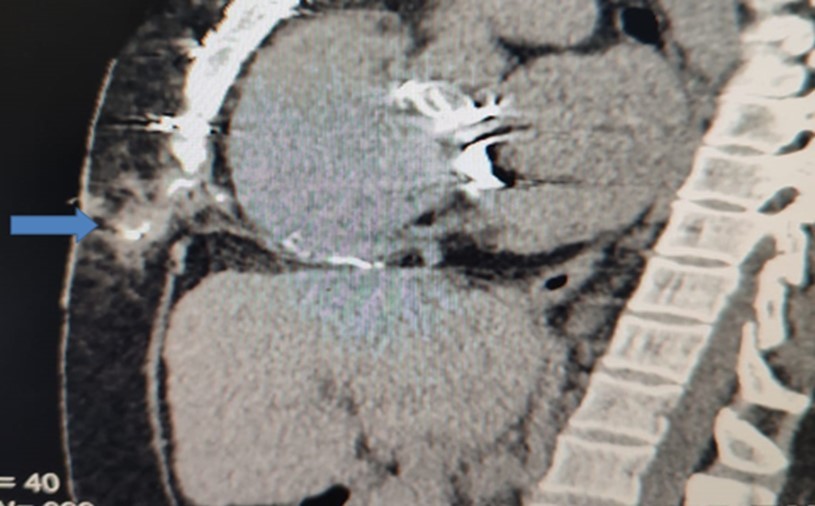

After weaning from cardiopulmonary bypass, as per institutional protocol for heart-valve operations, right atrial and /or right ventricular epicardial and diaphragmatic pacing wires (Quad Polar, 250 cm, Medical Concepts Europe (MCE), MCE Gemert, Netherlands) were inserted. Atrial wires were fixed with 5/0 prolene sutures taking superficial bites on the surface of the epicardial surface layer just to ensure gentle contact with the heart muscles and minimize complication rate 3, 5. The exit site in the epigastrium to the right of the midline was secured with a 2/0 silk suture. After an uneventful recovery in intensive care, each patient was transferred to the ward. As per institutional protocol, all postoperative cardiac surgical patients receive low molecular weight heparin subcutaneously as a prophylaxis against deep vein thrombosis The DVT-prophylaxis is continued until the day of discharge or when the patient is fully ambulatory. We do not stop the prophylaxis before temporary Pacemaker Wire-removal. On the 4th postoperative day, the pacing wires were pulled out with gentle traction. In centers other than ours, some surgeons only excise the external portion of the wires. This was complicated with chronic abscess and sinus formation years after surgery (Table 1). Diagnosis was confirmed radio-logically (Figure 1).

Figure 1.Sagittal CT-section of chest showing the extension of the sinus track containing the contrast

b) Computerized tomography with mild push of contrast to the sinus track (Figure 1)